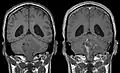

Les épendymomes supratentoriels (SE) représentent entre 40% et 60% des tumeurs intracrâniennes. Localisées au niveau supratentoriel, ces tumeurs apparaissent comme des grosseurs peu homogènes, présentant des zones kystiques, des calcifications mais également des zones hémorragiques et nécrosées.

Aspect radiologique à l’IRM en séquence T1 après injection de Gadolinium d’un épendymome supratentoriel, caractérisé par une lésion bien délimitée du lobe frontal gauche avec prise de contraste hétérogène et des zones de nécrose.